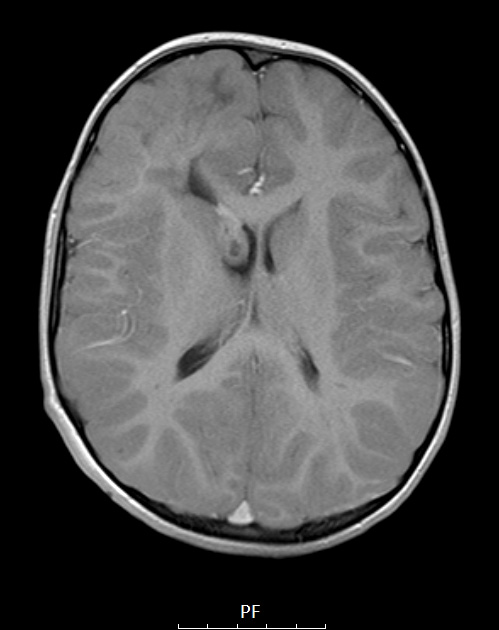

Washington University Experience | DEVELOPMENTAL MALFORMATIONS | Tuberous Sclerosis | 16A4 TS & SEGA (Case 16) T1W axial A - Copy

Neither the tuber nor SEGA enhance on this T1-weighted with contrast, sagittal (16A3) and axial (16A4) scans.